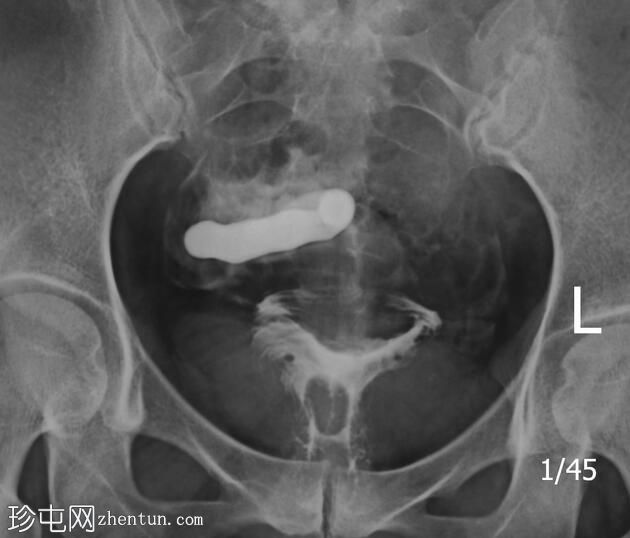

子宫体位于盆腔右侧旁中线,形态及轮廓正常。

宫颈管长度及黏膜表面正常,扩张正常。

右侧输卵管充盈,呈逐渐扩张,内有造影剂残留,无因输卵管积水导致的造影剂溢出。

左侧输卵管出现腹膜溢出。